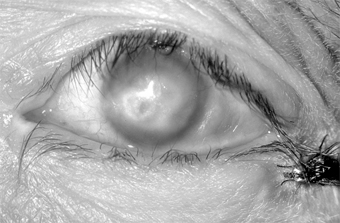

Conjunctival scarring is a frequent complication of trachoma and can destroy the ductules of the accessory lacrimal glands and obliterate the orifices of the lacrimal gland. These effects may drastically reduce the aqueous component of the precorneal tear film, and the film's mucous components may be reduced by loss of goblet cells. The scars may also cause distortion of the upper lid with inward deviation of individual lashes (trichiasis) or of the whole lid margin (entropion), so that the lashes constantly abrade the cornea. This often leads to corneal ulceration, bacterial corneal infections, and corneal scarring (Figure 5-2).

Figure 5-2: Advanced trachoma following corneal ulceration and scarring. Note the fly on the temporal aspect of the lower lid. The fly is a principal vector for trachoma.